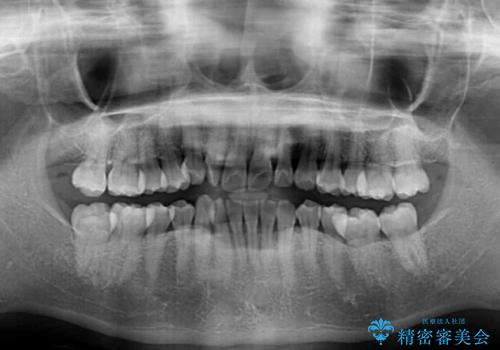

【モニター】上顎前突と奥歯の鋏状咬合 補助装置を用いたインビザライン矯正治療

- 前歯の歯列不正と奥歯の咬みにくさを気にして来院された患者様です。

インビザラインでの矯正治療を希望されていましたが、奥歯の咬み合わせがインビザライン単独では改善困難と判断されたので、補助装置を併用することとしました。

上顎最後臼歯は極端に外側を向いており、下顎骨に対して上顎骨が前方に位置していたため、補助装置により最後臼歯を一気に内側に引き込むとともに、上顎臼歯を後方移動させ、奥歯の咬み合わせが改善した後に、上下インビザラインにより歯列全体を整えていくこととしました。